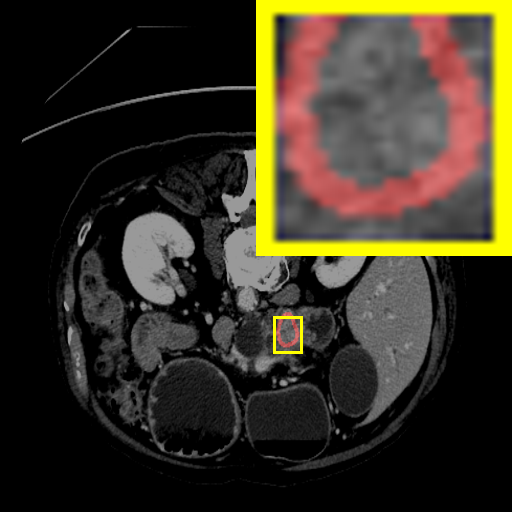

Figure 3: Qualitative comparison visualization of DEAP-3DSAM and baselines on four datasets.

IV-B2 Qualitative Performance Comparison

We also performed qualitative analysis on four datasets. As illustrated in Fig. 3, DEAP-3DSAM accurately identifies the target regions and closely matches their size. In contrast, 3DSAM-Adapter [3dsamadapter] exhibits limitations in matching the size and shape of the target regions. This proves that DEAP-3DSAM captures more complex image features, owing to its Dual Attention Prompter and Feature Enhanced Decoder. Furthermore, while these SAM-based methods are nearly capable of localizing the target regions, many traditional methods, i.e. UNETR++ [unetr++], Swin-UNETR [swinunetr], and TransBTS [transbts], struggle to achieve this. This highlights the potential of SAM-based methods for addressing complex 3D segmentation tasks.